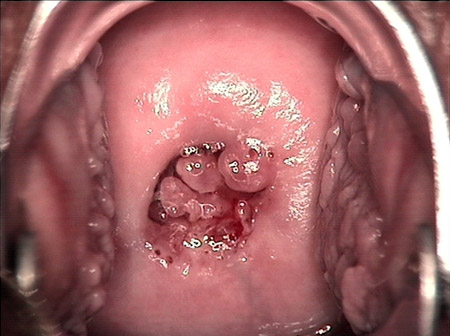

婦科leep錐切手術(shù) CIN2-3

• CIN 2-3 leep術(shù)后CIN 2-3 leep術(shù)后